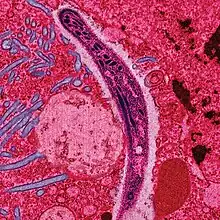

| False-colored electron micrograph showing a malaria sporozoite migrating through the midgut epithelium of a rat | |